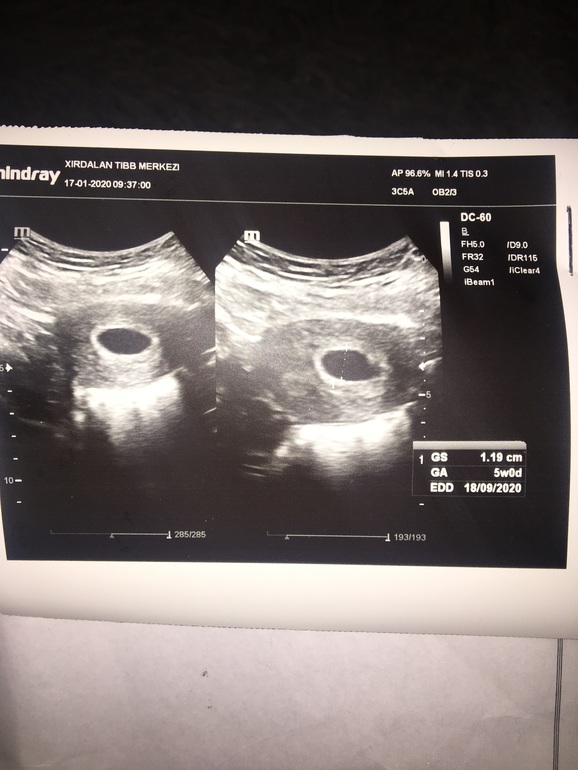

Сегодня была на узи. Последние мес были 8.12

На УЗИ поставили суров 5 недель. Увидели пя размер 1.19 мм и желточный мешок 0,20см. НО НЕ УИДЕЛИ ЭМБРИОН. рано ли? До этого было 2 замершие боюсь. Но врач не опытный отправил домой жди 2 недели . Или будет мазать или увидем эмбрион. Просто ждать? Гениколога спросила может сдать анализ может кровь густая как сказали девочки тут. Она нет если увидим эмбрион будем лечить и все.